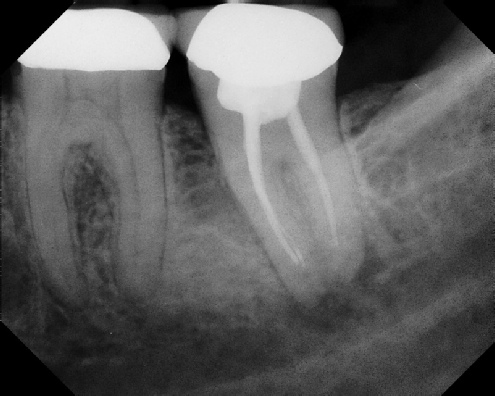

Root Canal Retreatment - Meriden 8 mos. recall Post-op Pre-op